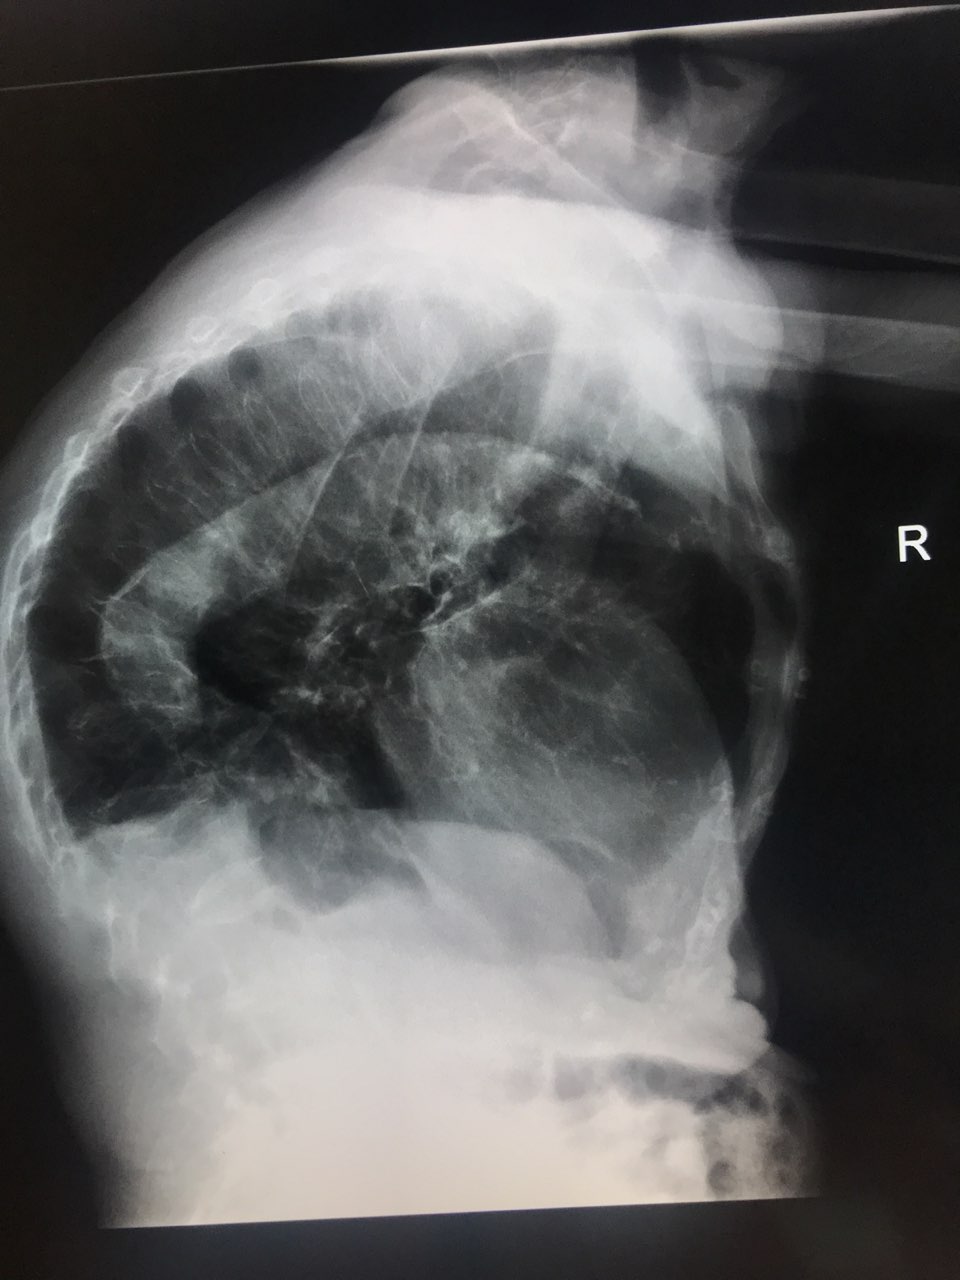

Огнестрельное ранение шеи. Пуля задела спинной мозг, у пациента - квадриплегия (паралич обоих рук и ног)

Огнестрельное ранение шеи. Пуля задела спинной мозг, у пациента - квадриплегия (паралич обоих рук и ног)

этот мскт

этот мскт

Это 3D моделирование КТ.

Это 3D моделирование КТ.